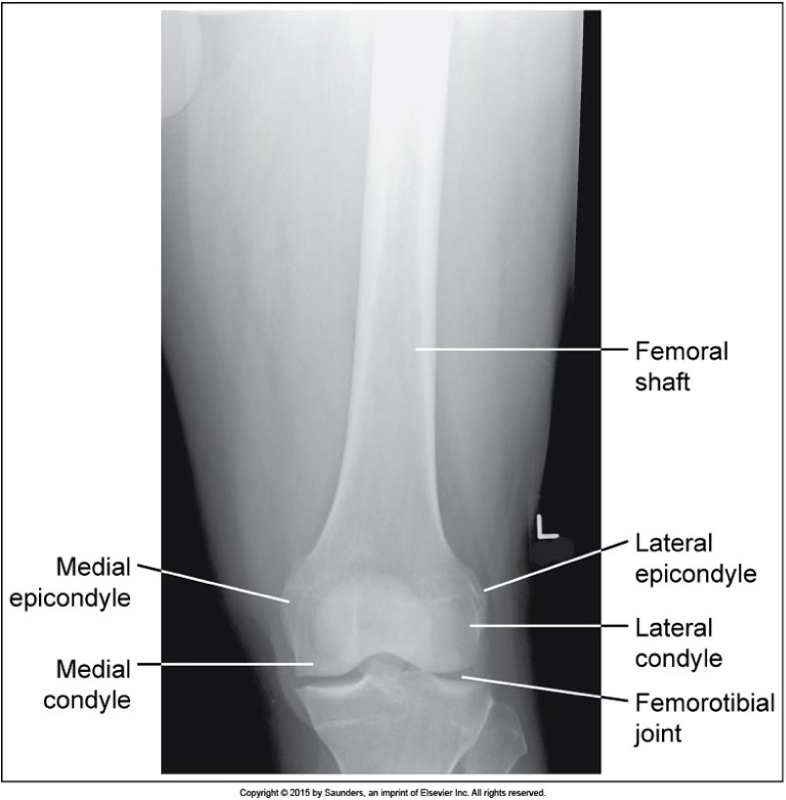

AP femur

accurate positioning